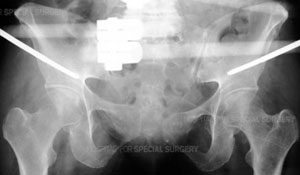

ARadiograph of the pelvis demonstrating application of a pelvic external fixator.

Patients with pelvic fractures may require one or more surgical procedures. The surgeon may begin with an External Fixation (Ex-Fix) technique in which an open or closed reduction is performed and the bones are then held in place using an external fixator, or frame. This is done by threading pins into the bone on either side of the fracture. These pins are then connected to rods outside the skin, which form a frame.